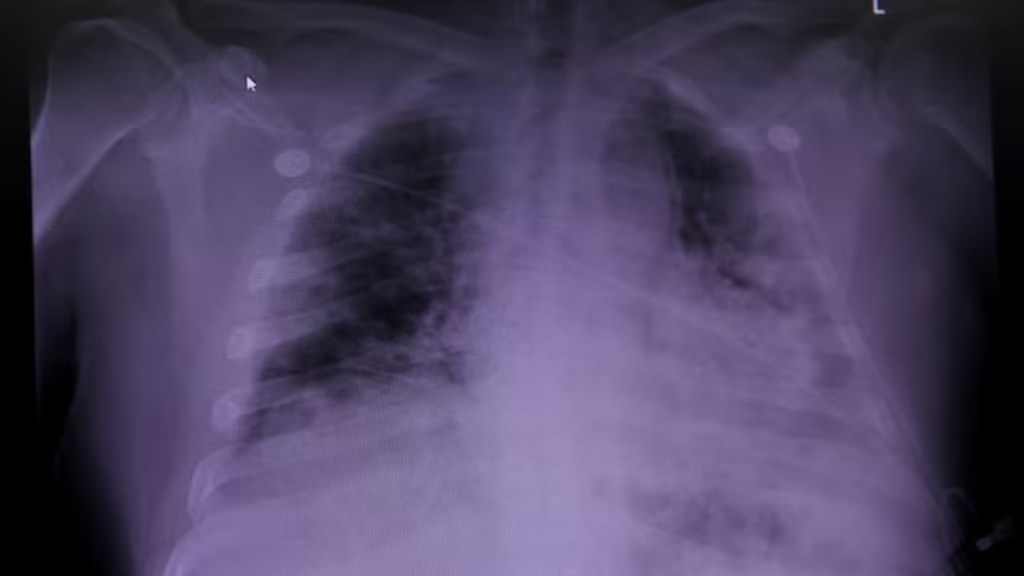

According to the US National Heart, Lung, and Blood Institute (NIH), idiopathic pulmonary fibrosis (IPF) is a severe chronic lung disease that affects the tissue surrounding the air sacs, or alveoli, in the lungs. The condition occurs when the lung tissue becomes thick and stiff for unknown reasons. Over time, this leads to permanent scarring, known as fibrosis, which progressively impairs the patient’s breathing. Individuals with a history of smoking or a family history of IPF are at higher risk. The risk also increases with age, making older adults more susceptible to developing the disease.

The scarring makes it harder to breathe and for oxygen to move from the lungs to the rest of the body. In healthy lungs, oxygen easily passes through the walls of the air sacs into tiny blood vessels and into the bloodstream. But in IPF, the walls of the air sacs get thicker, making it difficult for oxygen to pass into the blood.